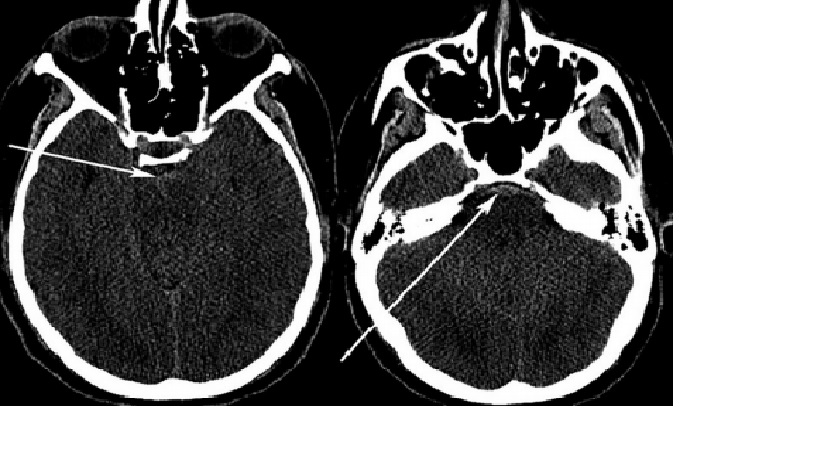

Một người đàn ông 23 tuổi đến khoa cấp cứu vì cơn đau đầu đột ngột sau khi nâng tạ trong phòng tập thể dục. BN mô tả cơn đau đầu là ” cơn đau tồi tệ nhất của cuộc đời mình”. CT đầu không cản quang cho thấy máu xung quanh bể trung não và bể trước cầu (perimesencephalic and prepontine cisterns). Chụp mạch máu không cho thấy nguyên nhân chảy máu. BN được MRI não và cột sống cổ, không có nguyên nhân gây chảy máu. BN được theo dõi 8 ngày sau khi xuất huyết, và được chụp mạch máu lập lại kết quả âm tính. Bệnh nhân xuất viện về nhà vào ngày thứ 10 sau xuất huyết dưới nhện tình trạng bình thường

Nhận xét: Trường hợp này minh họa lâm sàng điển hình cho một xuất huyết dưới nhện quanh trung não, với cận lâm sàng đầy đủ tìm kiến nguồn xuất huyết. Diễn biến của bệnh lành tính thường thấy ở những bệnh nhân bị xuất huyết dưới nhện quanh trung não.